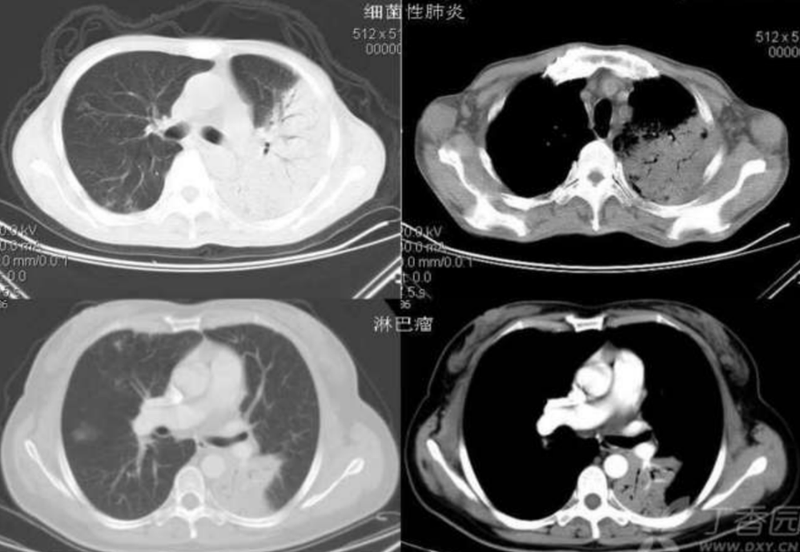

细支气管造影征

该征最多见于细支气管肺泡癌,表现为病灶内细管状或条状气体样低密度,条状或管状直径小于 1mm 。形成机制是由于CT扫描层面和充气支气管所在平面相平行所致。

细支气管肺泡癌一般分为三个类型:

1、孤立型病变:多在肺外围胸膜下周围,病变形态规则或不规则;

2 、多发结节型:大小不等的结节散布于 肺的一叶或多叶,有时甚至两肺均可受累,结节之间可见正常肺组织;

3、 弥漫型:病灶多叶或两肺弥漫分布。病变的位置对于病变的性质很重要,空泡征和细支气管征多位于孤立结节的中外 2/3 ,而良性结节多位于结节的内 2/3 ,该征相结合其所在的位置,可以初步断定病变的性质。

需要注意的是该征相和枯枝征及空气支气管造影征在含义上是有所不同的。大家可以同以前介绍过的相关征象中去细细体味其差别。